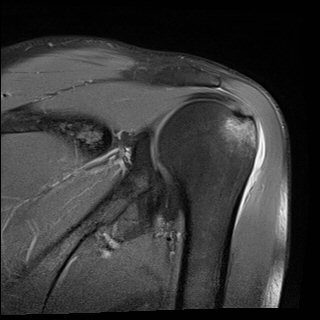

ÀÚ±â°ø¸í°Ë»ç

»ó¿Ï°ñµÎ ´ë°áÀý °ß¿­°ñÀý

±×·¯³ª º» Áõ·Ê¿¡¼­¿Í °°ÀÌ »ó¿Ï°ñµÎÀÇ ¹Ì¼¼°ñÀýÀº ¹æ»ç¼±°Ë»ç¿¡¼­ È®ÀÎÀÌ µÇÁö ¾ÊÀ¸¹Ç·Î

¹æ»ç¼±°Ë»ç¿¡¼­ ÀÌ»ó ¼Ò°ßÀÌ ¾øÀ¸¸é¼­ ½ÉÇÑ ÅëÁõ°ú ±Ù¾àÁõÀ» º¸ÀÌ´Â °æ¿ì´Â ¹Ýµå½Ã ÄÄÇ»ÅÍÃÔ¿µÀ̳ª

ÀÚ±â°ø¸í°Ë»ç¸¦ ½ÃÇàÇÏ¿© °ñÀý ¿©ºÎ¸¦ È®ÀÎÇØ¾ßÇÑ´Ù.